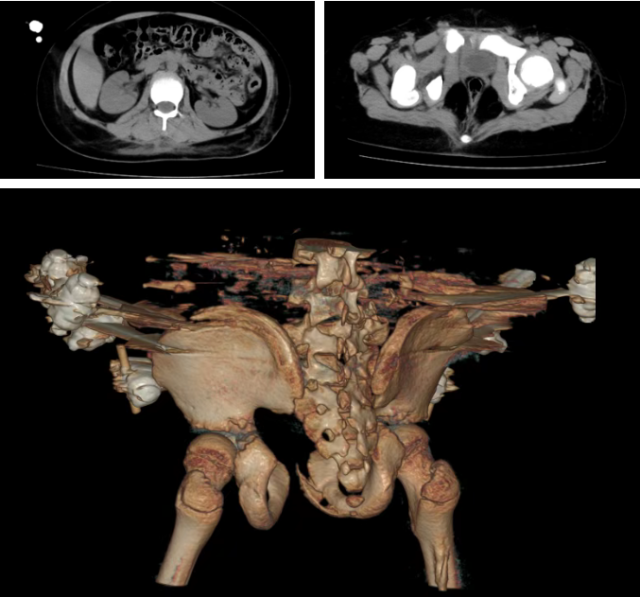

患儿术后影像,可见积血已消除、骨折已固定